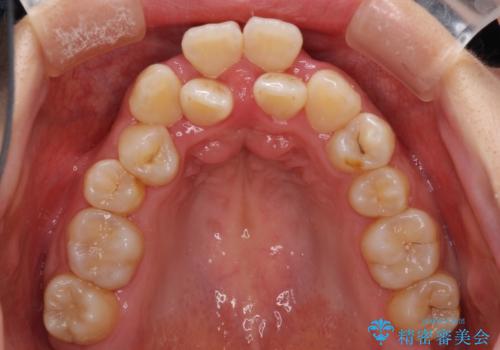

前後に重なった前歯 ワイヤー装置と急速拡大装置を併用したインビザライン矯正

- 前歯の著しい叢生とクロスバイトを気にして来院された患者様です。

叢生が強いため、一見すると抜歯矯正と判断したくなりますが、下顎臼歯が舌側に倒れていることから、上顎骨を側方拡大し、非抜歯矯正の可能性を検討することとしました。

急速拡大装置による上顎骨の側方拡大が思った以上にうまくいき、非抜歯での矯正が可能となりました。

内側に倒れていた下顎の臼歯は起き上がり、清掃性も大幅に改善されました。